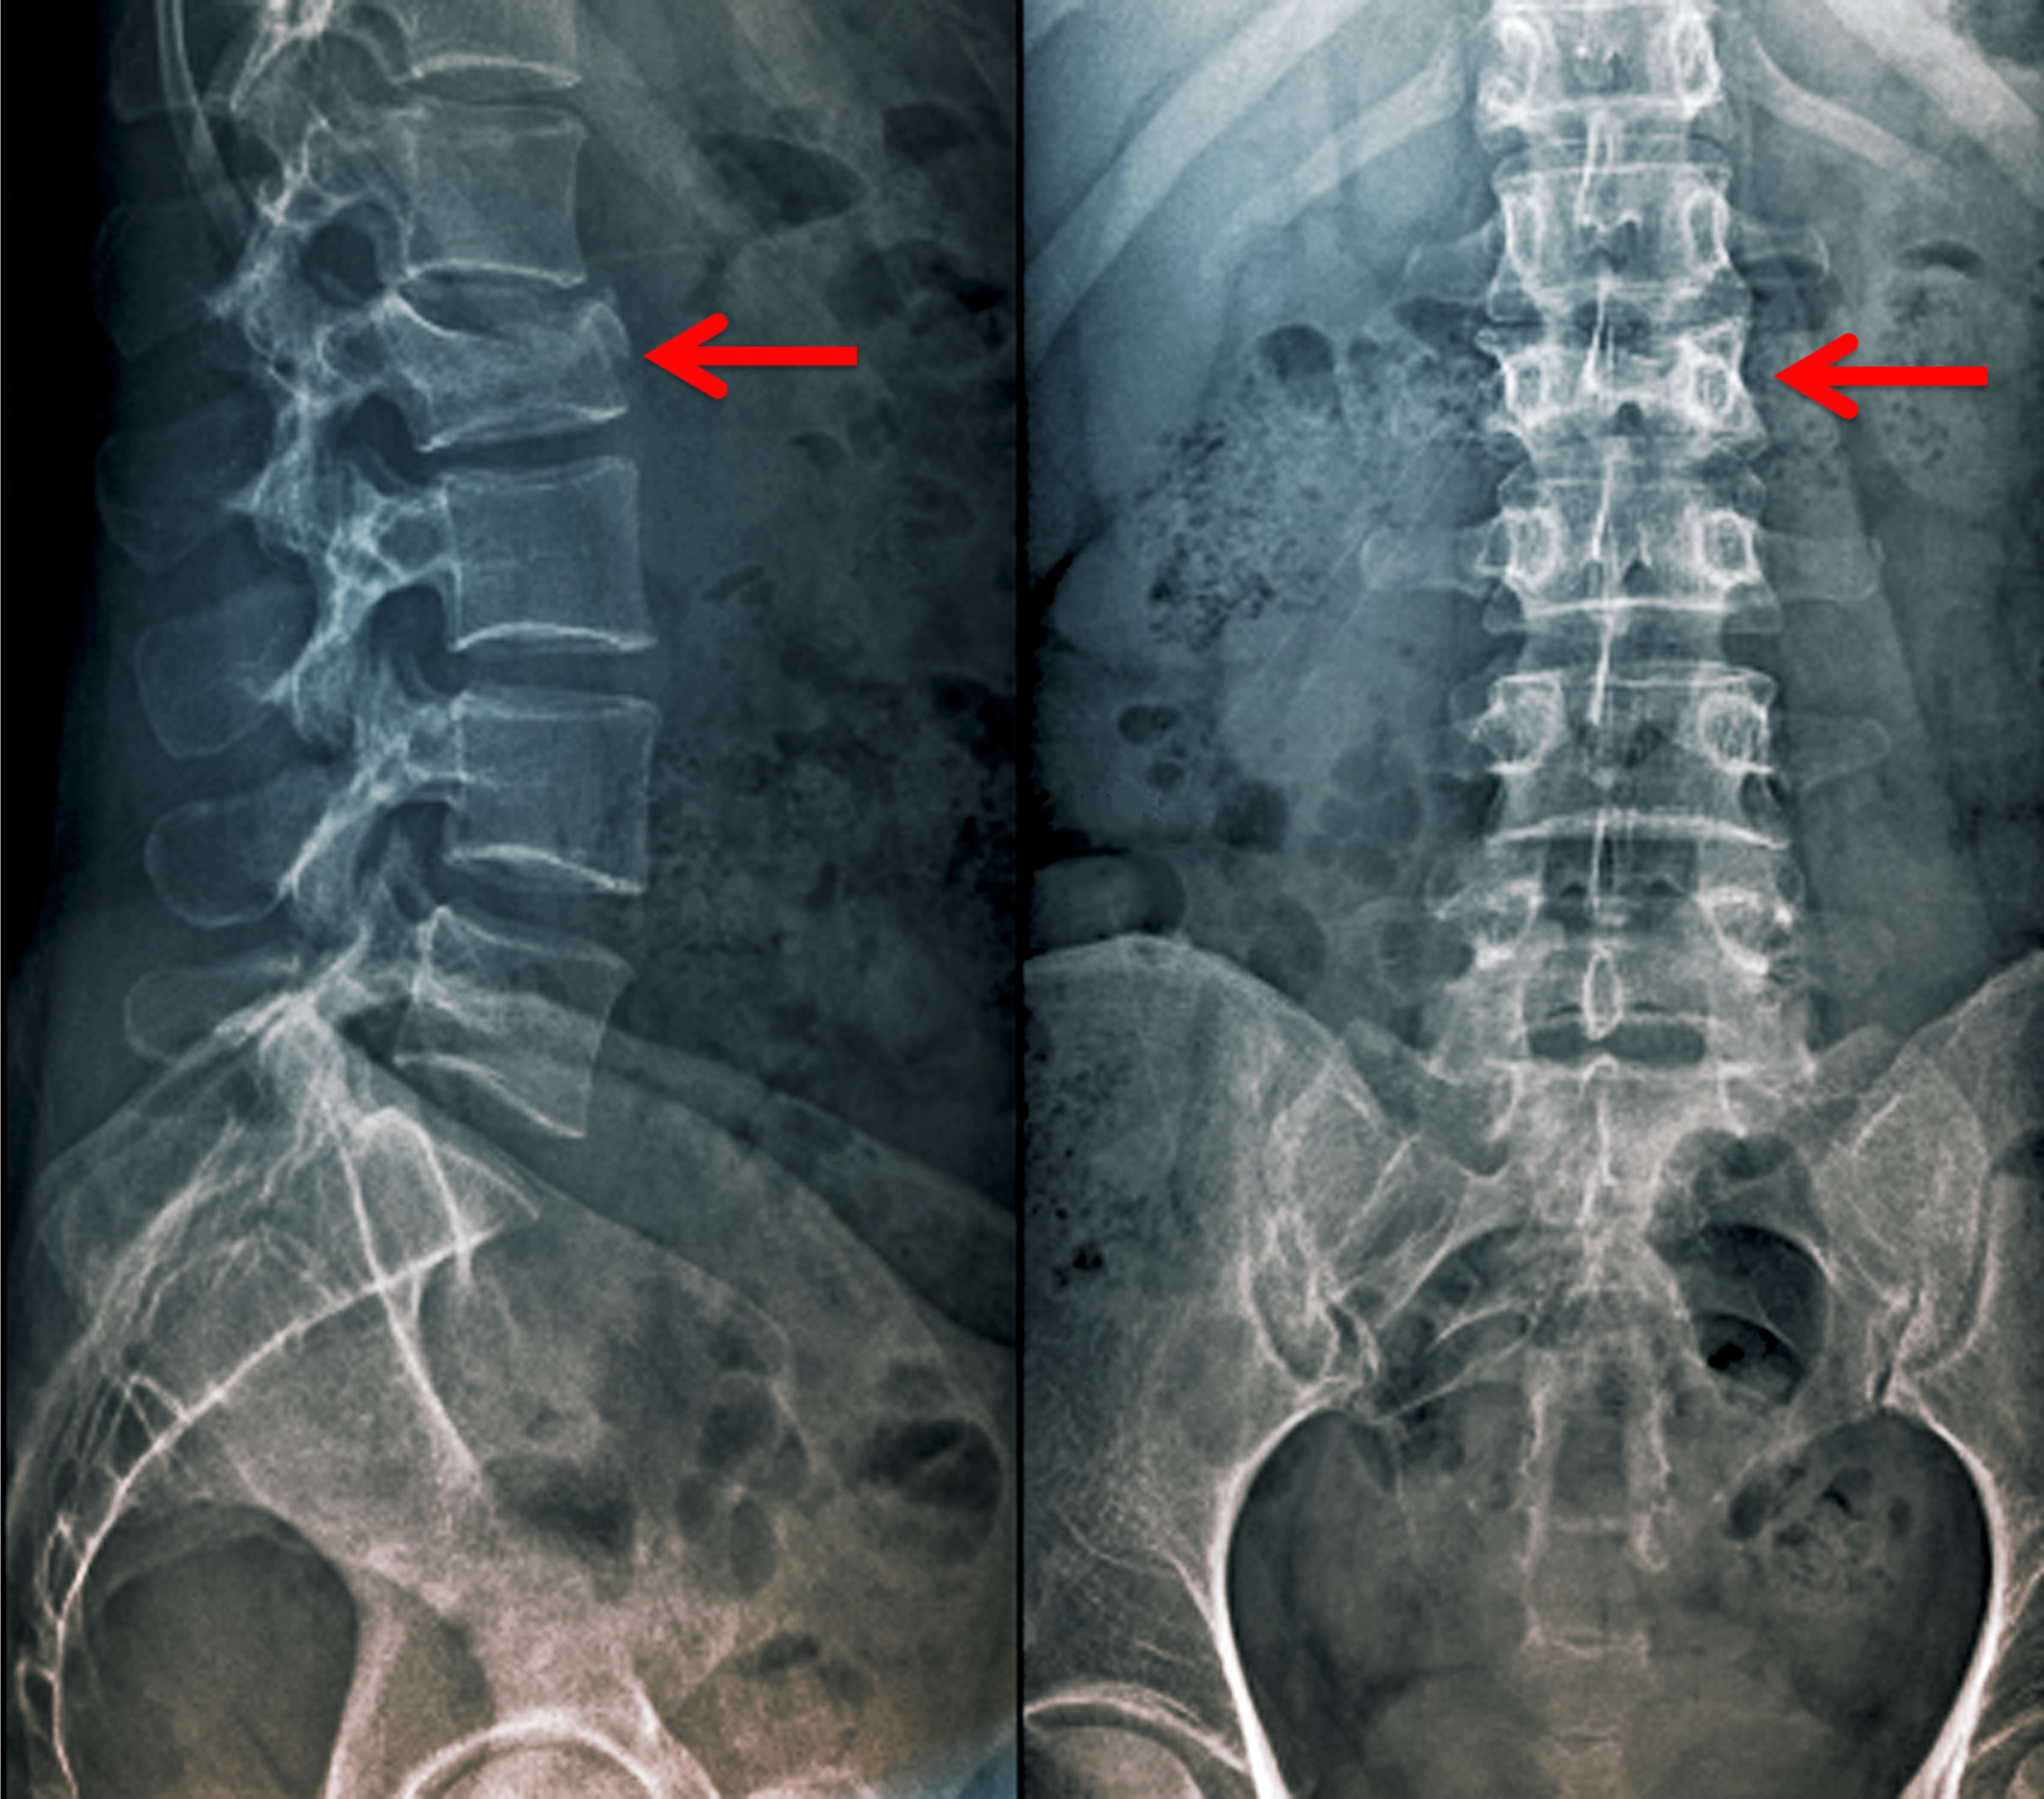

- La enfermedad de Paget, también llamada osteítis deformante, es un proceso crónico. Es una enfermedad del esqueleto en cuya primera fase aumenta la resorción ósea producida por los osteoclastos (fase osteolítica-destructiva), seguida de formación de un nuevo hueso, duro, denso y menos vascularizado que el anterior (fase osteoblástica-esclerótica), lo que da pie a un tejido óseo anómalo, muy propenso a la deformidad y las fracturas.